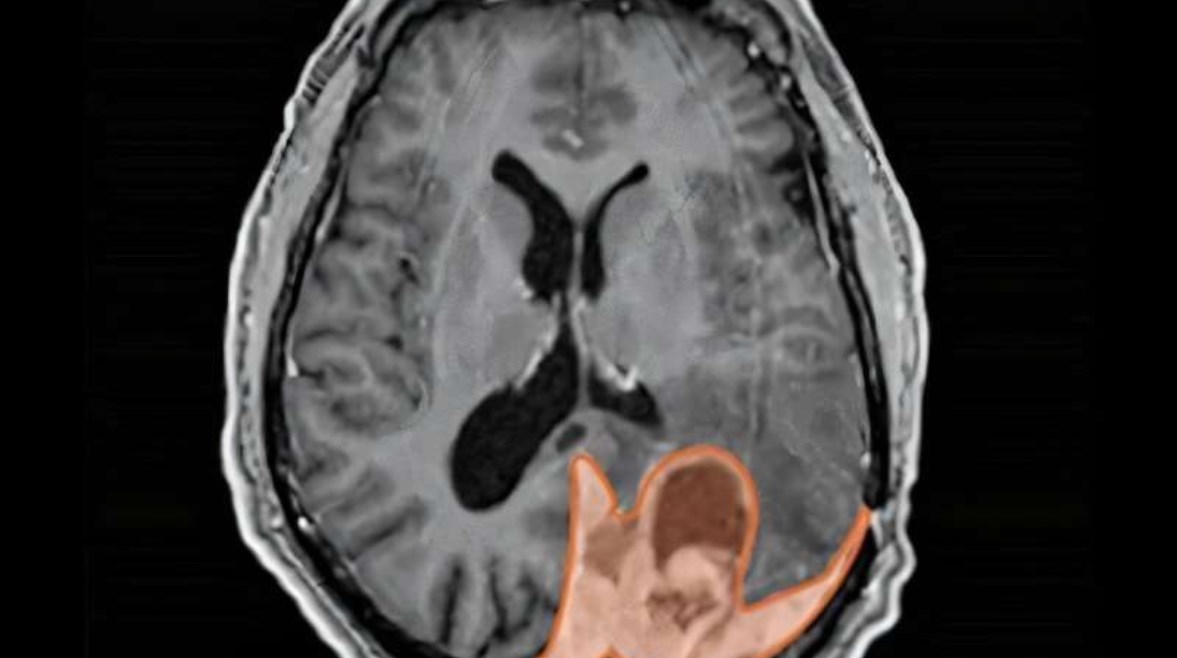

أورام المخ

تستخدم نساء كثيرات وسائل منع الحمل عن طريق الحقن العضلي، ولكن قد لا يدرك بعضهن ارتباط هذه الحقن بأورام المخ مثل الورم السحائي، وهو ما تشير إليه أبحاث علمية حديثة.

وبحث الطبيب ديفيد رالي الحاصل على درجة الدكتوراه، أخصائي الأورام الإشعاعية، حول الآليات البيولوجية التي تُغذي نمو السرطان السحائي بالمخ، واهتمت أبحاثه بفهم العلاقة بين الورم السحائي والبروجيستيرون الاصطناعي "MPA" المُستخدم في وسائل منع الحمل عن طريق الحقن، بحسب موقع "مديكال إكسبريس".

ووجد الباحثون في دراسة فرنسية أجريت عام 2024، أن النساء اللاتي استخدمن وسائل منع الحمل عن طريق الحقن العضلي لمدة عام واحد على الأقل كان لديهن خطر متزايد بنسبة خمسة أضعاف للإصابة بالورم السحائي مقارنة بمن لم يستخدمن هذه الوسائل.

يُعد الورم السحائي أحد أنواع أورام الدماغ القليلة الأكثر شيوعًا لدى النساء عن الرجال، أي أكثر شيوعًا بحوالي مرتين إلى أربع مرات.

ووفقًا للأبحاث، فإن الحمل قد يُسرع نمو الورم السحائي، وهذا النمط نفسه يُلاحظ لدى النساء اللواتي استخدمن العلاج الهرموني بعد انقطاع الطمث، وأيضًا لدى النساء اللواتي استخدمن وسائل منع الحمل عن طريق الحقن العضلي، يمكن أن يتراجع الورم السحائي بعد الولادة وبعد التوقف عن العلاج الهرموني، وتشير البيانات السريرية والوبائية بالتأكيد إلى وجود ارتباط ميكانيكي بين هذه النتائج.

ما مدى خطورة الورم السحائي؟

عادةً ما يكون ورم الدماغ خطيرًا، لكن هناك درجات مختلفة منه، تعد حوالي 65% إلى 70% من الأورام السحائية هي أورام من الدرجة الأولى ذات الخطورة العالية، وتُعتبر هذه الأورام غير خبيثة، وعادةً ما تُزال جراحيًا أو تُعالج بالعلاج الإشعاعي، وإذا بقي ورم، يُمكن علاجه أيضًا بالعلاج الإشعاعي. يبقى ما يصل إلى 95% من مرضى الدرجة الأولى على قيد الحياة بعد خمس سنوات، حسب العمر وحجم الورم المُزال.